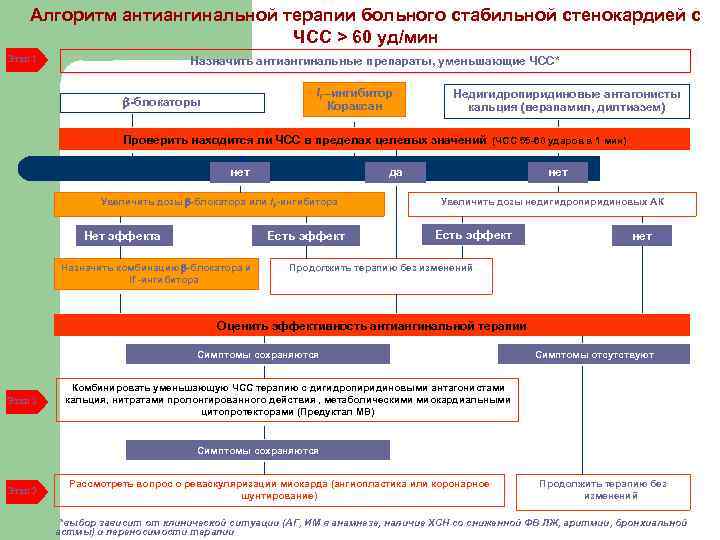

Алгоритм антиангинальной терапии больного стабильной стенокардией с ЧСС > 60 уд/мин Этап 1 Назначить антиангинальные препараты, уменьшающие ЧСС* If –ингибитор Кораксан -блокаторы Недигидропиридиновые антагонисты кальция (верапамил, дилтиазем) Проверить находится ли ЧСС в пределах целевых значений (ЧСС 55 -60 ударов в 1 мин) нет Увеличить дозы -блокатора или If -ингибитора Нет эффекта Есть эффект Назначить комбинацию -блокатора и If -ингибитора нет да Увеличить дозы недигидропиридиновых АК Есть эффект нет Продолжить терапию без изменений Оценить эффективность антиангинальной терапии Симптомы сохраняются Этап 2 Симптомы отсутствуют Комбинировать уменьшающую ЧСС терапию с дигидропиридиновыми антагонистами кальция, нитратами пролонгированного действия , метаболическими миокардиальными цитопротекторами (Предуктал МВ) Симптомы сохраняются Этап 3 Рассмотреть вопрос о реваскуляризации миокарда (ангиопластика или коронарное шунтирование) Продолжить терапию без изменений *выбор зависит от клинической ситуации (АГ, ИМ в анамнезе, наличие ХСН со сниженной ФВ ЛЖ, аритмии, бронхиальной астмы) и переносимости терапии